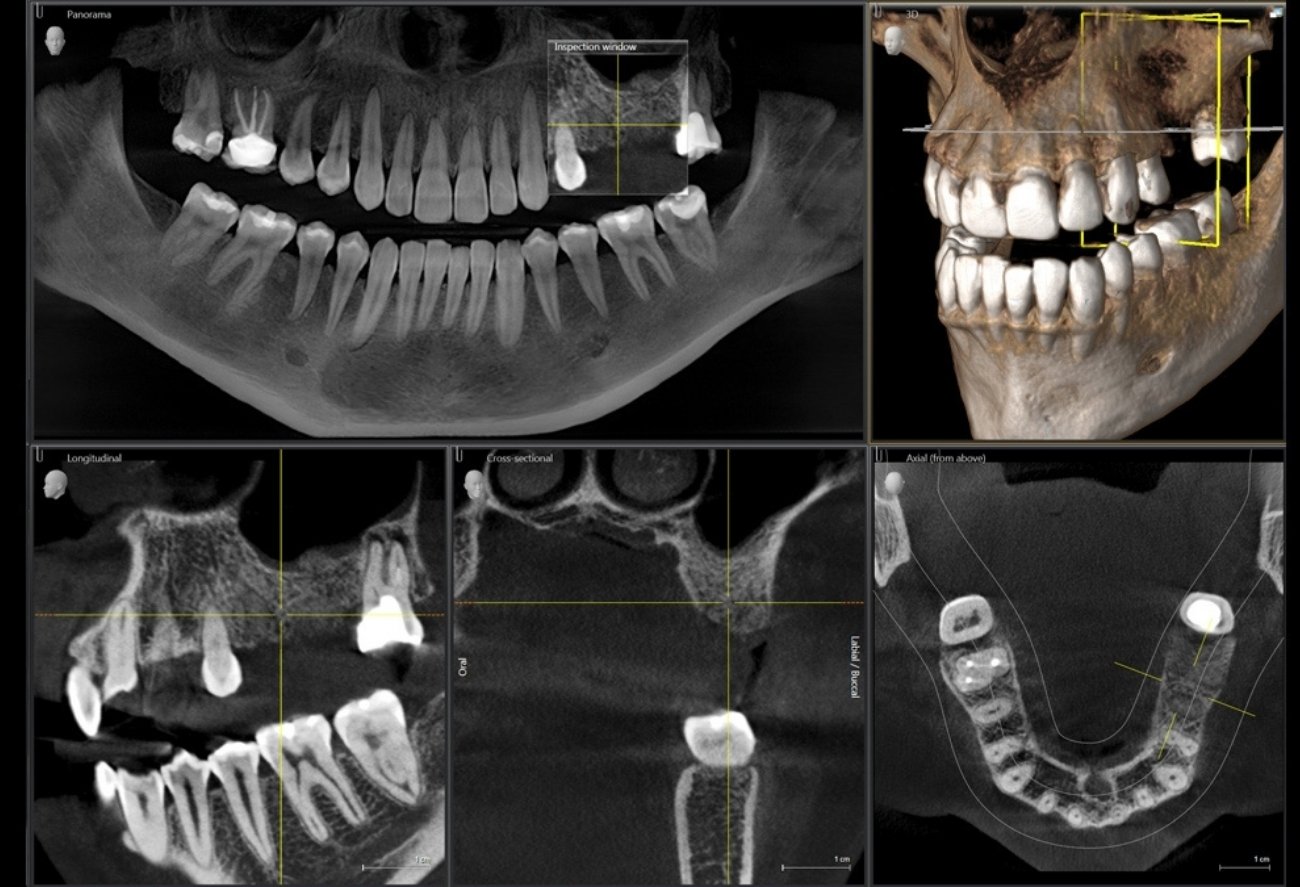

Приклади 3D-зображень: